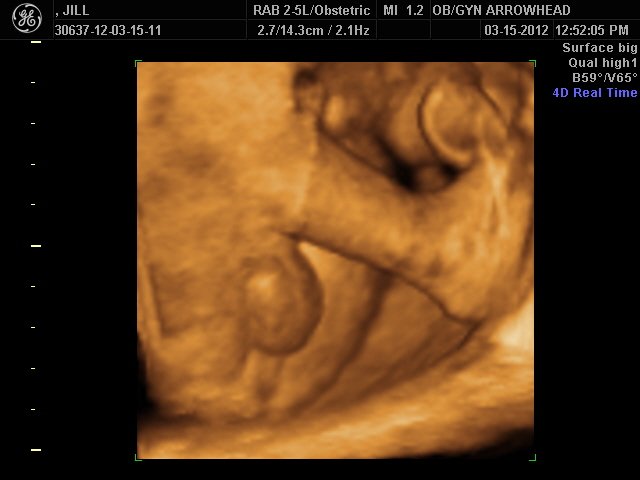

We offer complimentary 3D/4D Ultrasounds to all our OB patients around 30 weeks! The following photos are some examples of our work, shown with permission from our patients.